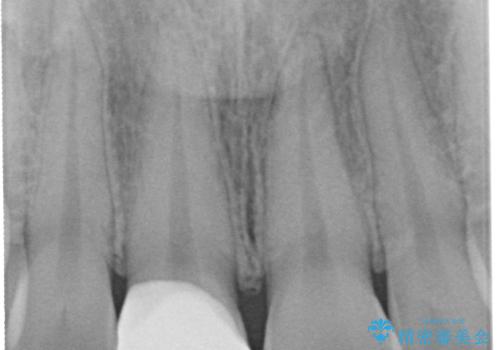

土台の形を整えて、精度の高いシリコーンによる型どりを行いました。

セラミックが入るまでの間は仮歯にしています。

樹脂の材料では再現できない自然な前歯に仕上がりました。